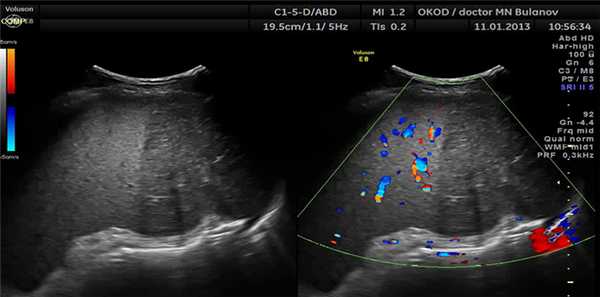

- Спленомегалия. УЗИ сканограмма

- Спленомегалия при портальной гипертензии. УЗИ сканограмма